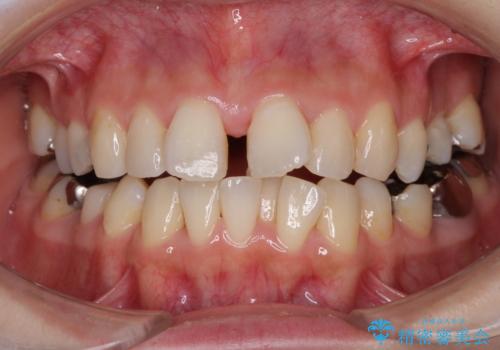

- 上下のデコボコと奥歯の咬みにくさを気にして来院された患者様です。

上顎骨の幅が下顎骨よりも小さいので、拡大装置により骨幅を広げて上下関係を改善し、その後インビザラインにて歯並びを整えることとしました。

上下の骨幅を改善したことで、スムーズに歯列矯正を行うことができました。

矯正治療中に近医で銀歯を外す治療を開始したため、治療後に奥歯の咬み合わせが不十分ですが(こちらは近医での治療により改善するとのこと)、歯列と咬み合わせが改善され、患者様には大変満足していただきました。